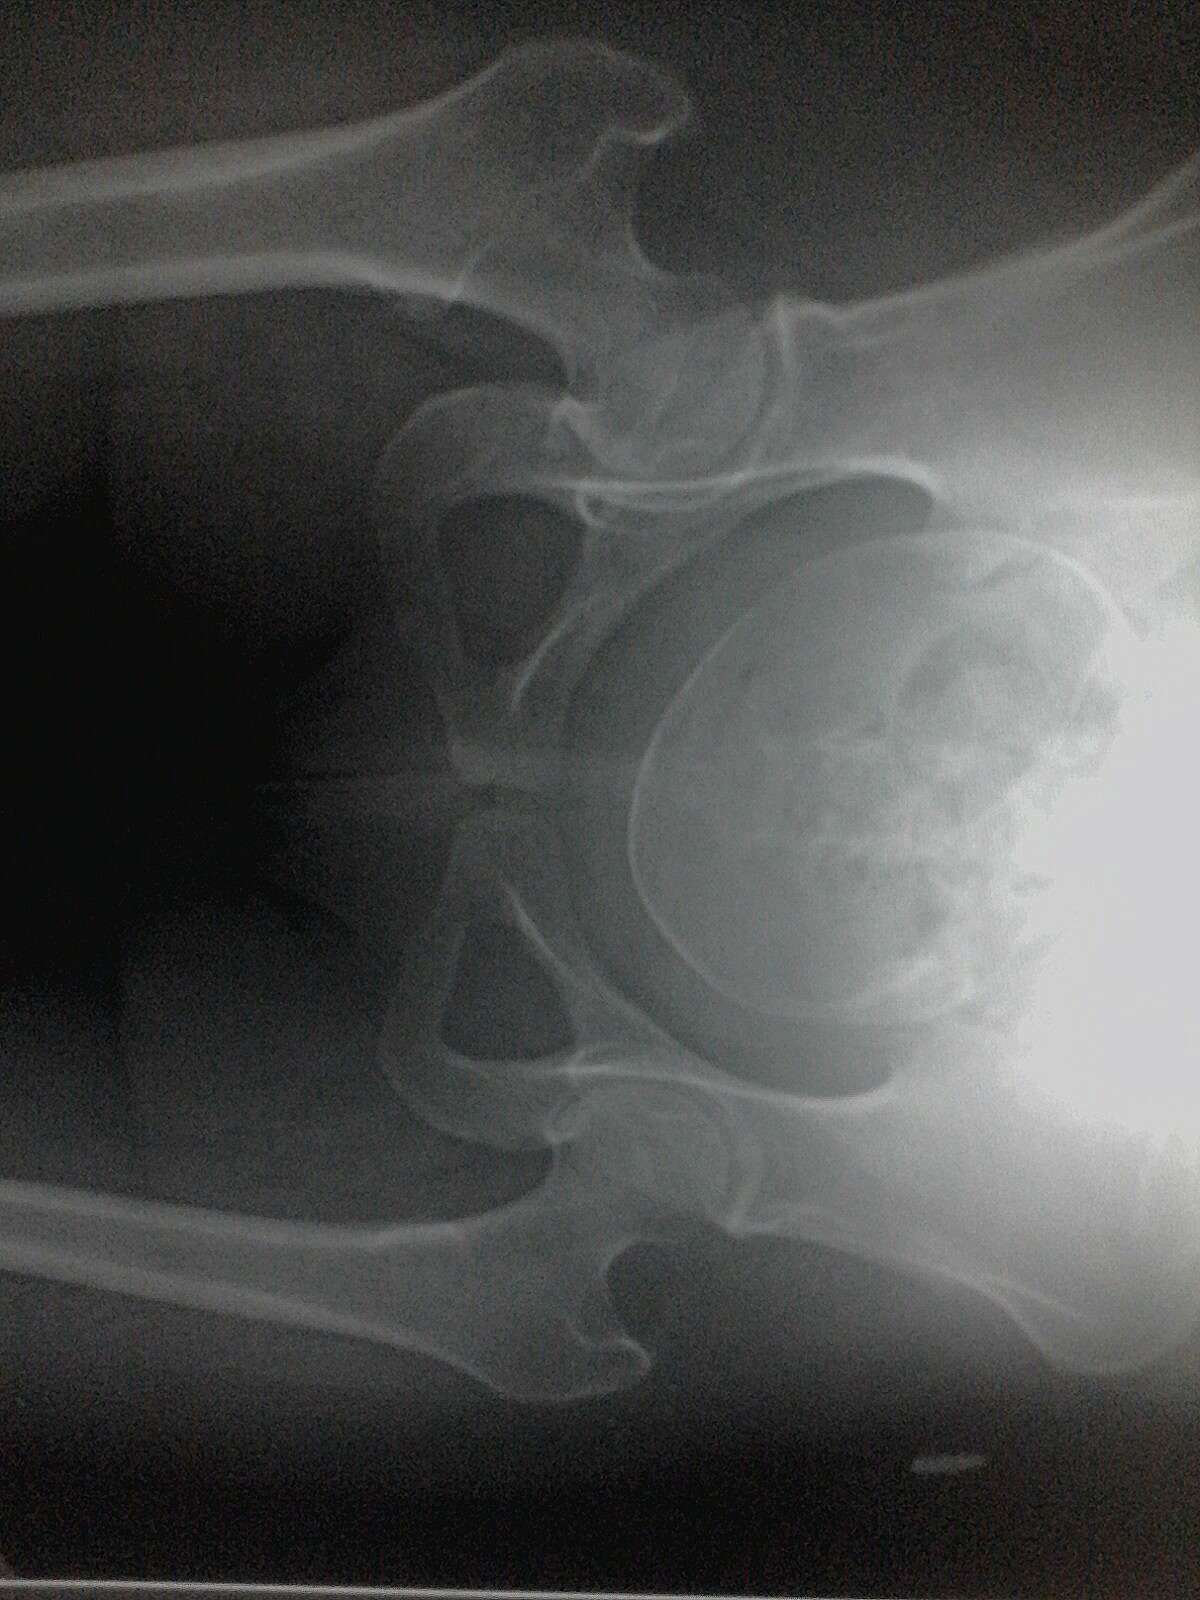

Diagnostico medico por Imagen